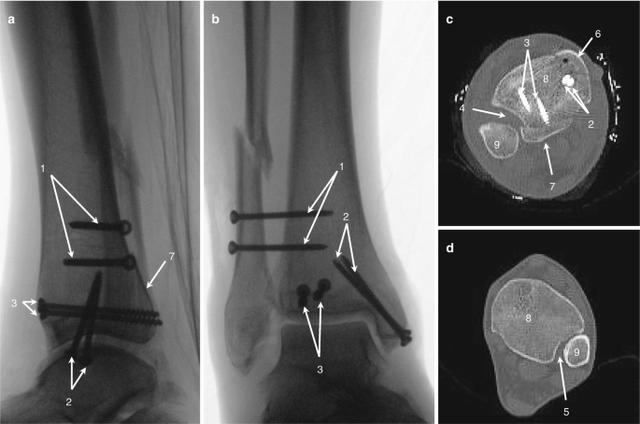

Hinsichtlich der Operationsverfahren dominieren bei pertrochantären Femurfrakturen die DHS (Dynamic Hip Screw) mit einem Anteil von 57,5%, gefolgt von der intramedullären Stabilisierung mit 38,3%. Bei medialer Schenkelhalsfraktur verteilen sich die OP-Methoden auf Duokopf-FEP (43,7%), TEP (28,6%), monopolare FEP (14,1%) und Verschraubung (8,9%). Dabei zeigt sich bei der intramedullären Stabilisierung im Vergleich zur DHS eine höhere Rate an intraoperativen Komplikationen und Implantatfehlagen.

Bei den Operationsverfahren gab es deutliche Unterschiede zwischen den Frakturlokalisationen. Bei pertrochantären Femurfrakturen wurden am häufigsten die DHS (Dynamic Hip Screw) Methode (57,5%) und die intramedulläre Stabilisierung (38,3%) eingesetzt. Bei medialen Schenkelhalsfrakturen verteilten sich die OP-Methoden auf Duokopf-FEP (43,7%), TEP (28,6%), monopolare FEP (14,1%) und Verschraubung (8,9%).

Es zeigte sich auch eine unterschiedliche Komplikationsrate je nach Operationsverfahren. Die intramedulläre Stabilisierung war mit einer höheren Rate an intraoperativen Komplikationen (1,8% vs. 1,1%) und Implantatfehllagen (0,47% vs. 0,12%) verbunden.

Ein signifikant erhöhter Anteil von Notfalloperationen wurde bei pertrochantären Femurfrakturen festgestellt (33,9% vs. 17,1%). Bei diesen Frakturen erfolgte zudem in 82,9% der Fälle (im Vergleich zu 64,1% bei medialer SHF) eine operative Versorgung innerhalb von 24 Stunden nach Aufnahme. Die dominierenden Operationsverfahren bei pertrochantären Femurfrakturen waren die DHS (57,5%) und die intramedulläre Stabilisierung (38,3%). Letztere wurde häufiger in Häusern der Schwerpunktversorgung eingesetzt.

Bei der intramedullären Stabilisierung traten im Vergleich zur DHS häufiger intraoperative Komplikationen (1,8% vs. 1,1%) und Implantatfehllagen (0,47% vs. 0,12%) auf. Insgesamt betrug die Komplikationsrate 24,4%, wobei eine signifikante Verringerung bei Häusern der Maximalversorgung festgestellt wurde (20,8%). Der Mobilisierungsgrad bei Entlassung bzw. Verlegung war bei medialer SHF und PTH vergleichbar, wobei 58% der vor der Fraktur selbstständig gehfähigen Patienten dieses Ausgangsniveau wieder erreichten.